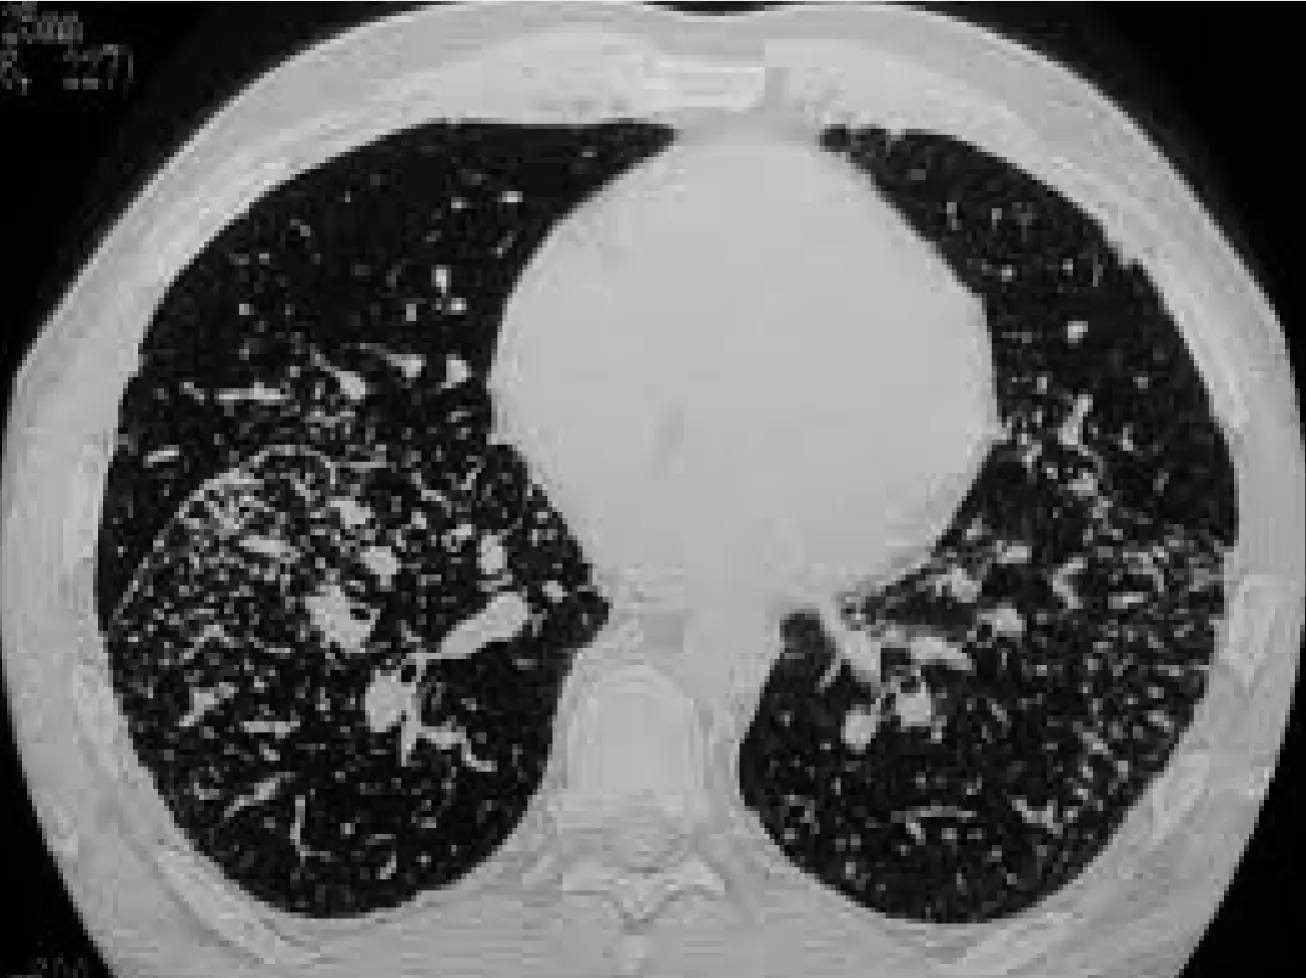

Staging of Sarcoidosis on the Basis of Chest Radiographs

| STAGE | Description | Frequency |

|---|---|---|

| STAGE 0 | No abnormalities | 5%–10% |

| STAGE 1 | Lymphadenopathy (fig. A) | 50% |

| STAGE 2 | Lymphadenopathy + pulmonary infiltration (fig. B) | 25%–30% |

| STAGE 3 | Pulmonary infiltration (fig. C) | 10%–12% |

| STAGE 4 | Fibrosis | 5% (up to 25% during the course of the disease) |